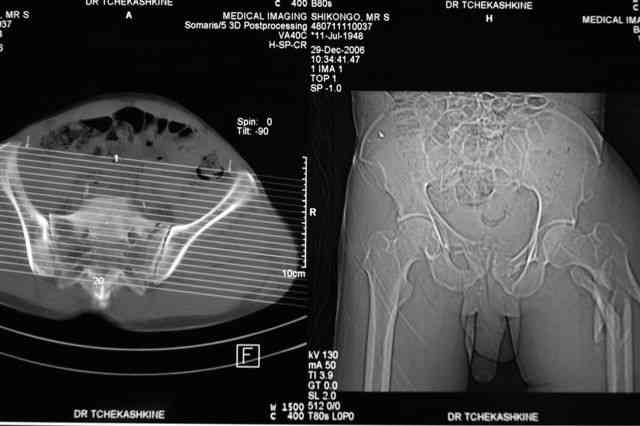

В приложении отправляю послеопер. снимки бедра и лодыжки обсуждаемого вчера больного.

В приложении послеоперационные картинки.